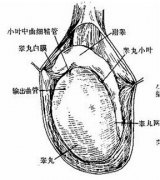

都市男性睾丸生精功能障碍出现的病因

生精功能障碍要做哪些检查

生精功能障碍有哪些危害?

生精功能异常会出现什么症状?

生精功能障碍要做哪些检查?